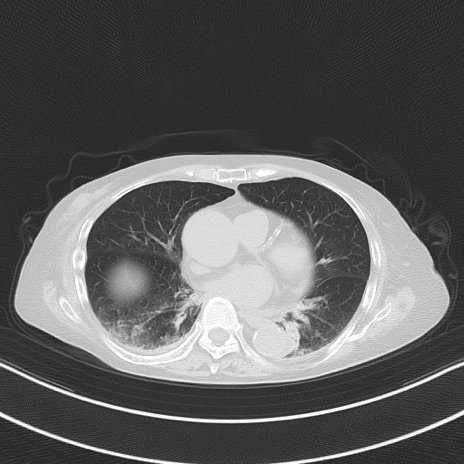

横断像

他院CT